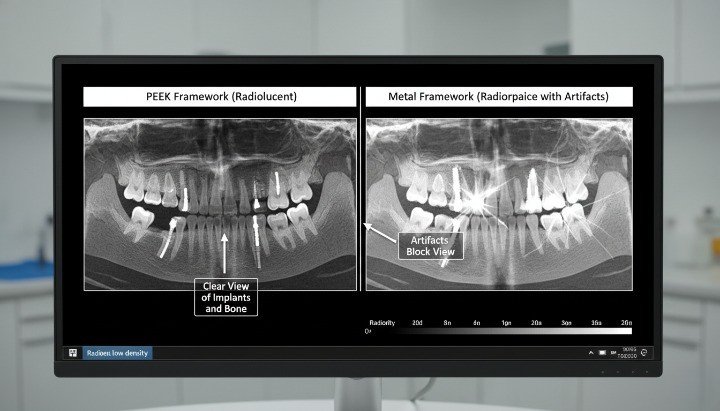

Radiolucency and Imaging Advantages

PEEK is radiolucent, which means it does not interfere with X-ray, CBCT, or CT imaging. Clinicians can clearly visualize surrounding bone and soft tissue without metallic artifacts.

This imaging transparency improves diagnostics and follow-up. It also supports accurate assessment of marginal bone levels and peri-implant tissue health.

Dive deeper, radiolucency is especially valuable in temporary restorations, healing components, and frameworks where clinicians want unobstructed imaging during healing and evaluation phases.

Radiographic and MRI Compatibility

PEEK is radiolucent and MRI compatible without artifacts.

Titanium causes imaging artifacts and beam hardening.